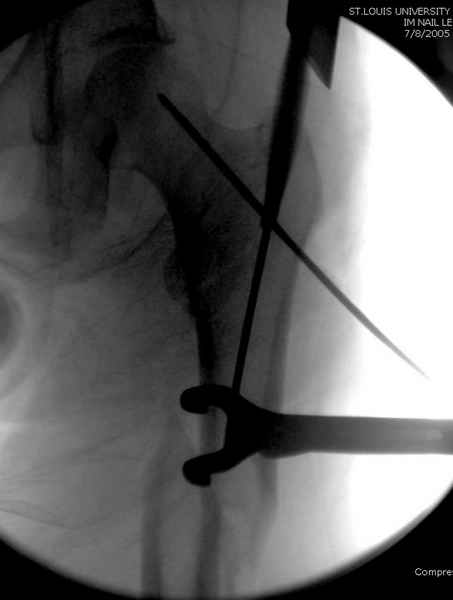

Как раз недавно у меня был примерный случай: больному 36 лет, поступил ночью, травма в результате мотоциклетной аварии, кроме чрезвертельного и спирального перелома левого бедра имеется переломы костей предплечья с этой же стороны. Скелетное вытяжение, а на следующий день больной про оперирован на ортопедическом столе с дистракцией. Чтобы не расколоть чрезвертельный перелом провели временную спицу ближе к переднему кортексу, из малого разреза костодержатель для репозиции, а фиксацию провели антиградным штифтом. Этапы операции на снимках.

Джолдас Кульджанов